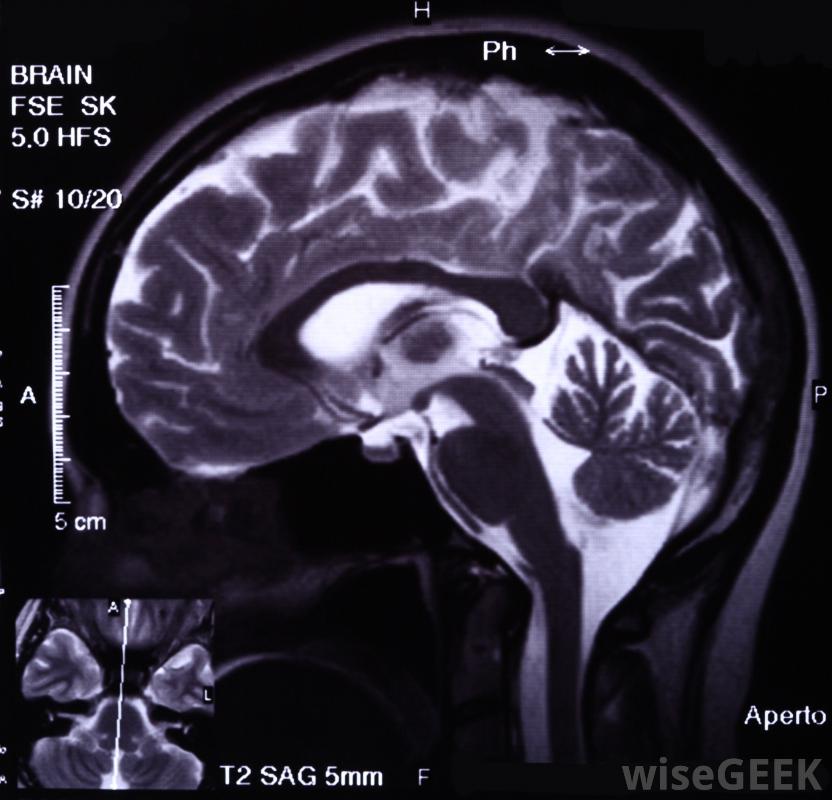

腦膜瘤約占大腦腫瘤的三分之一,之所以稱之為腦膜,是因為腦膜是保護大腦和脊髓的膜。顱窩腦膜瘤生長在凹陷處或周圍,或是凹處,在顱骨之間。最值得注意的是位于大腦底部的三個顱窩,它們容納了腦葉:前部的前顱窩;中間的顱窩,也被稱為基底的側面;后顱窩,位于大腦后部的下側。腫瘤也可以占據許多較小的顱窩中的一個,因此,腦膜瘤的診斷可能涉及頸靜脈窩、垂體窩、顳或顳下窩、翼腭窩或鎖骨上窩。腦膜瘤的發展是不可預測的,雖然并不常見,但腫瘤可能會影響多個顱窩前顱窩腦膜瘤會損害人的嗅覺,頸靜脈窩位于咽喉底部的頸靜脈切跡處。垂體窩是蝶骨內的一個小口袋,位于中顱窩。顳窩位于顱骨的兩側,是頜骨肌肉的所在地,就在顳下窩的上方和后方。翼腭窩位于上頜后面。鎖骨上窩位于鎖骨上方,鎖骨骨骨連接胸骨和肩部腦膜瘤通常是通過核磁共振(MRI)等腦成像來診斷的。顱窩腦膜瘤可根據其起源地進一步分類。通常根本不在顱窩,而是在許多可能的情況下,腫瘤生長到三個主要窩中的一個,可能帶有額外的標記,如蝶骨翼、矢狀竇旁、鞍上、巖骨、大孔、幕或斜坡腦膜瘤,以確定其確切的起源脊髓通常被包裹在被稱為腦膜的膜內,它能保護和緩沖長神經。顱窩腦膜瘤對個人健康的影響取決于腫瘤的類型——它的生長速度,主要發生在老年人的顱窩腦膜瘤幾乎都是良性的,可能超過一半是無癥狀的,但也可能出現嚴重的癥狀,當這些腫瘤增大到足以對控制中樞神經系統、感官或重要身體功能的大腦相鄰部分施加壓力時腦膜瘤通常生長在大腦和脊髓周圍的膜上,發生在前顱窩的腦膜瘤會損害嗅覺和視覺,或損害垂體活動性。中顱窩腦膜瘤會影響眼球運動和面部感覺,或對向大腦供血的頸內動脈施加危險的壓力。后顱窩是三個顱窩中最深和最大的,因為它包含腦干和小腦,控制著大腦的一切器官和精神活動。在這個區域生長的腫瘤會導致呼吸、吞咽和說話困難,損傷聽覺或味覺,或損害平衡和協調。對有癥狀的顱窩腦膜瘤,最有效的治療方法是手術切除,同時切除鄰近的腦組織或骨但是,與其他類型的腫瘤一樣,顱窩腦膜瘤可能是復雜的,不太明確,生長在顱骨內和周圍,需要更復雜的手術。無癥狀腦膜瘤的首選治療方案是不去管腫瘤并監測其活動性,如果有的話。中顱窩腦膜瘤會影響眼球運動。